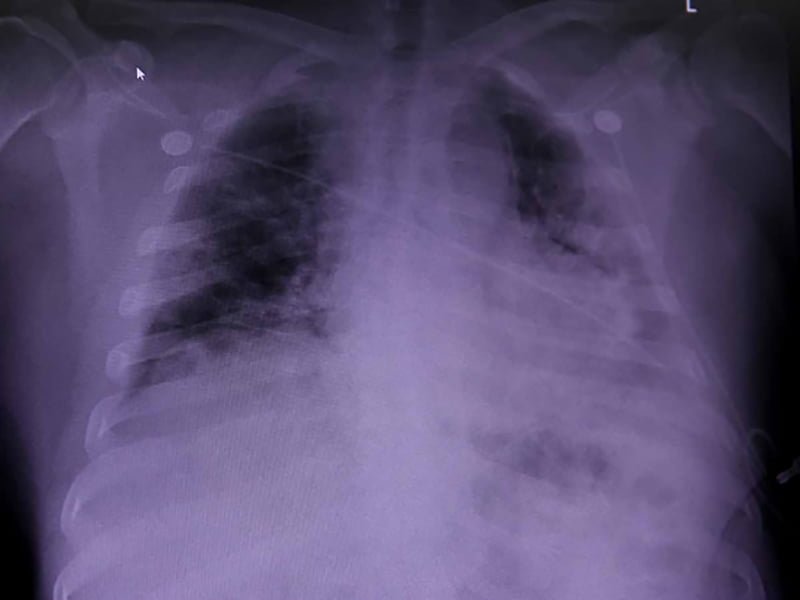

Por medio de gas xenón se pudieron obtener imágenes del daño pulmonar durante las resonancias magnéticas.

A través de esta técnica, los pacientes inhalan el gas durante una exploración por imágenes de resonancia magnética.

Sin embargo, los nuevos escáneres mostraron signos de daño pulmonar, al resaltar áreas donde el oxígeno no fluye fácilmente hacia la sangre, en los ocho que informaron falta de aire.

(Foto: Tomada de la BBC)